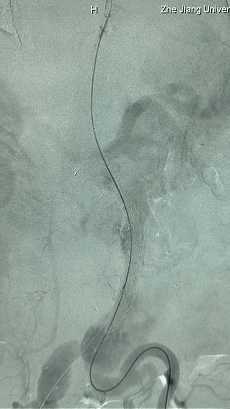

2. 左侧肱动脉入路,超选至降主动脉,更换8F-900mm长鞘,造影提示IV型胸腹主动脉瘤,累及双肾动脉。

3. 经右股动脉导入超硬导丝,然后导入先健G-Branch 胸腹主动脉主体覆膜支架TAAA3418120e7i1010 一枚,释放主体支架至内分支打开,然后经左侧肱动脉入路,抓捕预置导丝成功后,将长鞘进入内分支出口处。